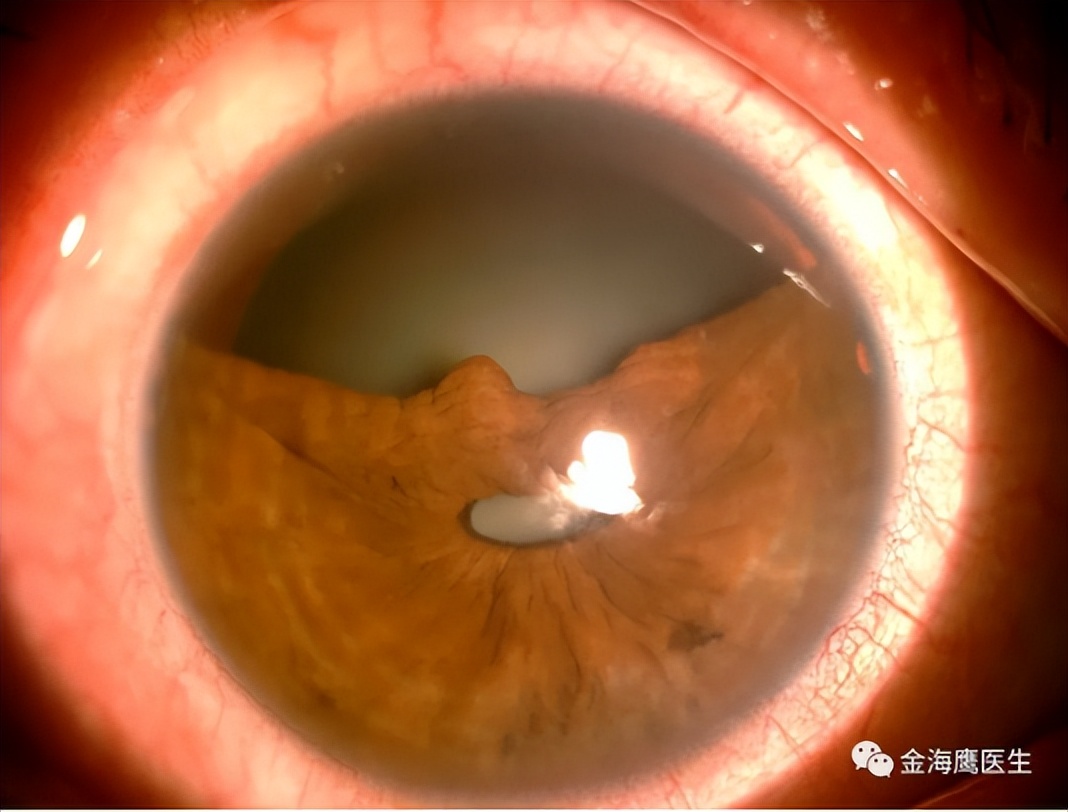

最后,金教授列举了一个临床病例,展示巩膜层间缝纫机技术的实际应用。患者右眼大范围虹膜根部离断,采用金教授原创的巩膜层间缝纫机技术进行了虹膜修复术,并植入散光矫正型人工晶状体,术后一天患者右眼眼前节正常解剖结构基本恢复,视力显著提高,且未出现低眼压、视网膜脱离等并发症。

图11. 术前患者眼前段照相

图12. 术后第一天患者眼前段照相